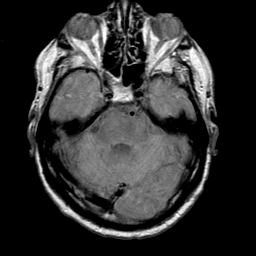

Meningioma, MR Study #1 -- Slice #5

[Home][Help][Clinical] Slice 5